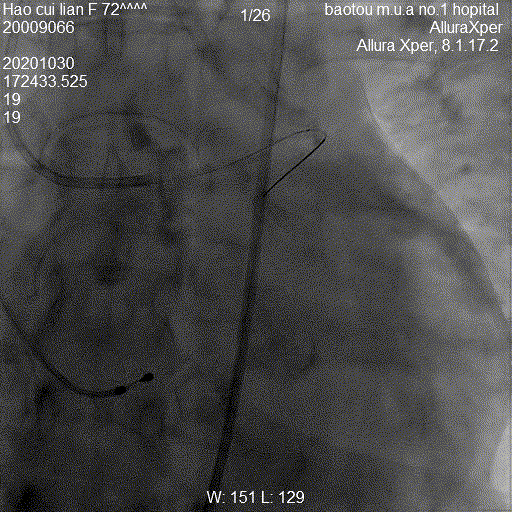

图:手术流程图